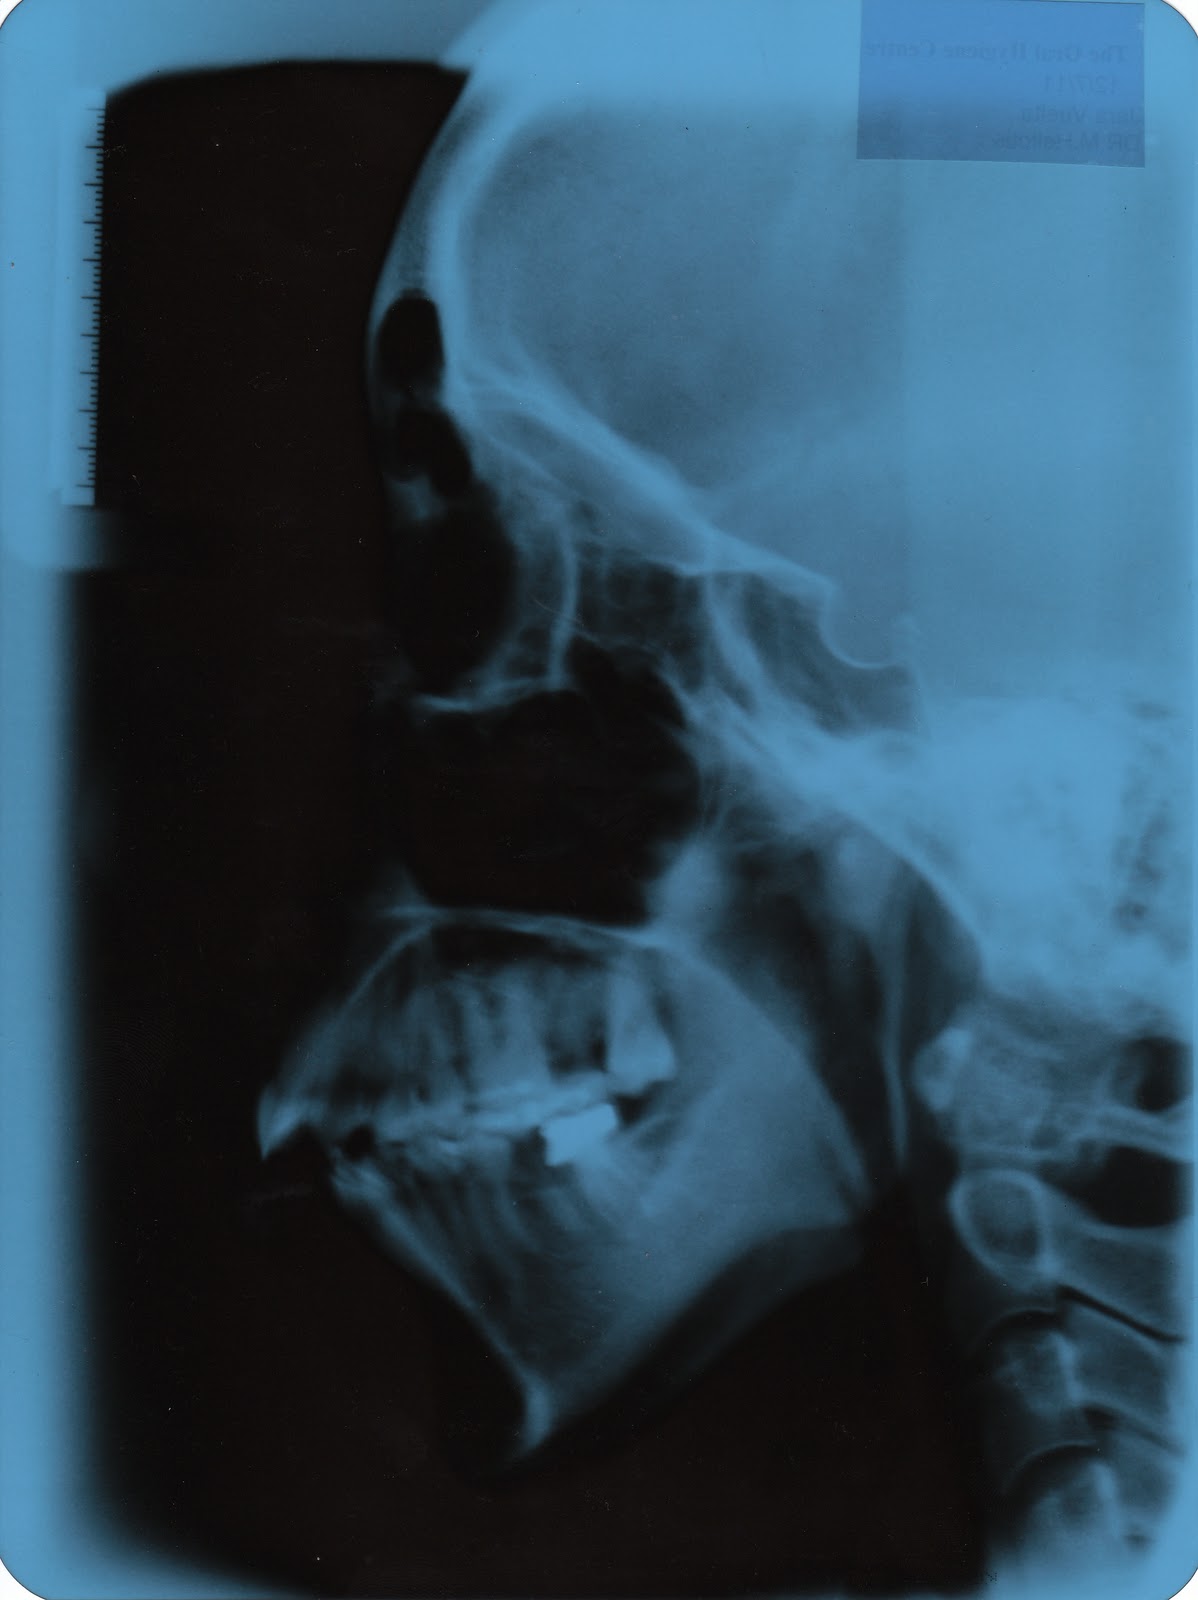

Double Jaw Surgery X Ray . what is double jaw surgery? double jaw surgery corrects both the upper and lower jaw at the same time. Most people undergo jaw surgery to treat. jaw surgery, also called orthognathic surgery, is surgery that helps align your upper jaw (maxilla) and lower jaw. You can see, quite clearly, the drastic change that took place on the operating. mouth breathing, dry mouth, jaw pain, difficulty chewing, and an inability to bite led me to double jaw surgery. Jaw surgery, or orthognathic surgery, corrects jaw problems and related conditions. They do a decent job of. Learn more about how this surgery works and how we can help.

Learn more about how this surgery works and how we can help. mouth breathing, dry mouth, jaw pain, difficulty chewing, and an inability to bite led me to double jaw surgery. Most people undergo jaw surgery to treat. You can see, quite clearly, the drastic change that took place on the operating. jaw surgery, also called orthognathic surgery, is surgery that helps align your upper jaw (maxilla) and lower jaw. what is double jaw surgery? They do a decent job of. double jaw surgery corrects both the upper and lower jaw at the same time. Jaw surgery, or orthognathic surgery, corrects jaw problems and related conditions.

Double Jaw Surgery X Ray They do a decent job of. Learn more about how this surgery works and how we can help. You can see, quite clearly, the drastic change that took place on the operating. They do a decent job of. jaw surgery, also called orthognathic surgery, is surgery that helps align your upper jaw (maxilla) and lower jaw. Most people undergo jaw surgery to treat. what is double jaw surgery? mouth breathing, dry mouth, jaw pain, difficulty chewing, and an inability to bite led me to double jaw surgery. double jaw surgery corrects both the upper and lower jaw at the same time. Jaw surgery, or orthognathic surgery, corrects jaw problems and related conditions.